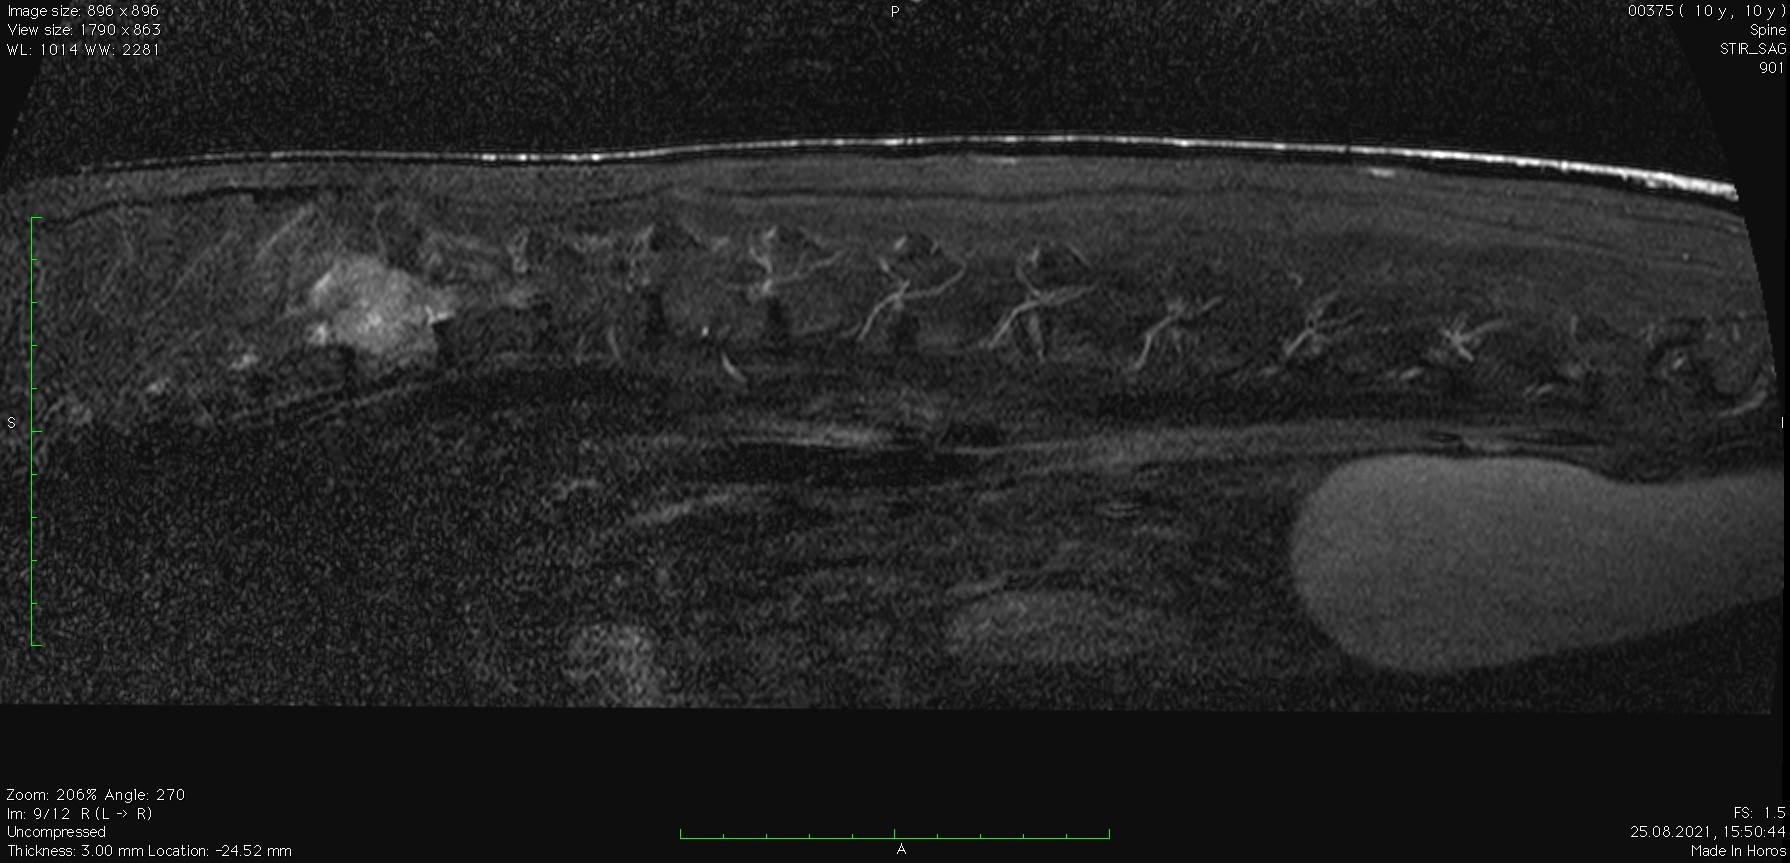

Заключение МРТ:

Признаки очагового образования с накоплением контраста в СМК на уровне Th10 (правая сторона) размером 2,2 х 2,3 см с поражением позвонка, окружающие ткани, выраженной компрессией СМ. С левой стороны на данном уровне отмечается артефакты. На уровне Th12-L2, L6-S1 отмечаются протрузии дисков.